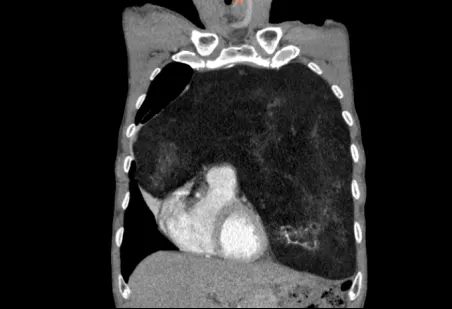

怀着忐忑的心情,家人陪同老人来到郑州大学第五附属医院胸外科就诊。完善胸部增强CT检查后,结果让经验丰富的高兴才主任也为之震惊:患者的前纵隔、左侧胸腔乃至部分右侧胸腔,被一个巨大的混杂密度团块所占据,其长径达23cm!这个巨大的瘤体几乎占满左侧胸腔,严重挤压纵隔使其向右移位,左肺因受压而萎陷。这正是导致老人长期胸闷、呼吸不畅的“罪魁祸首”。